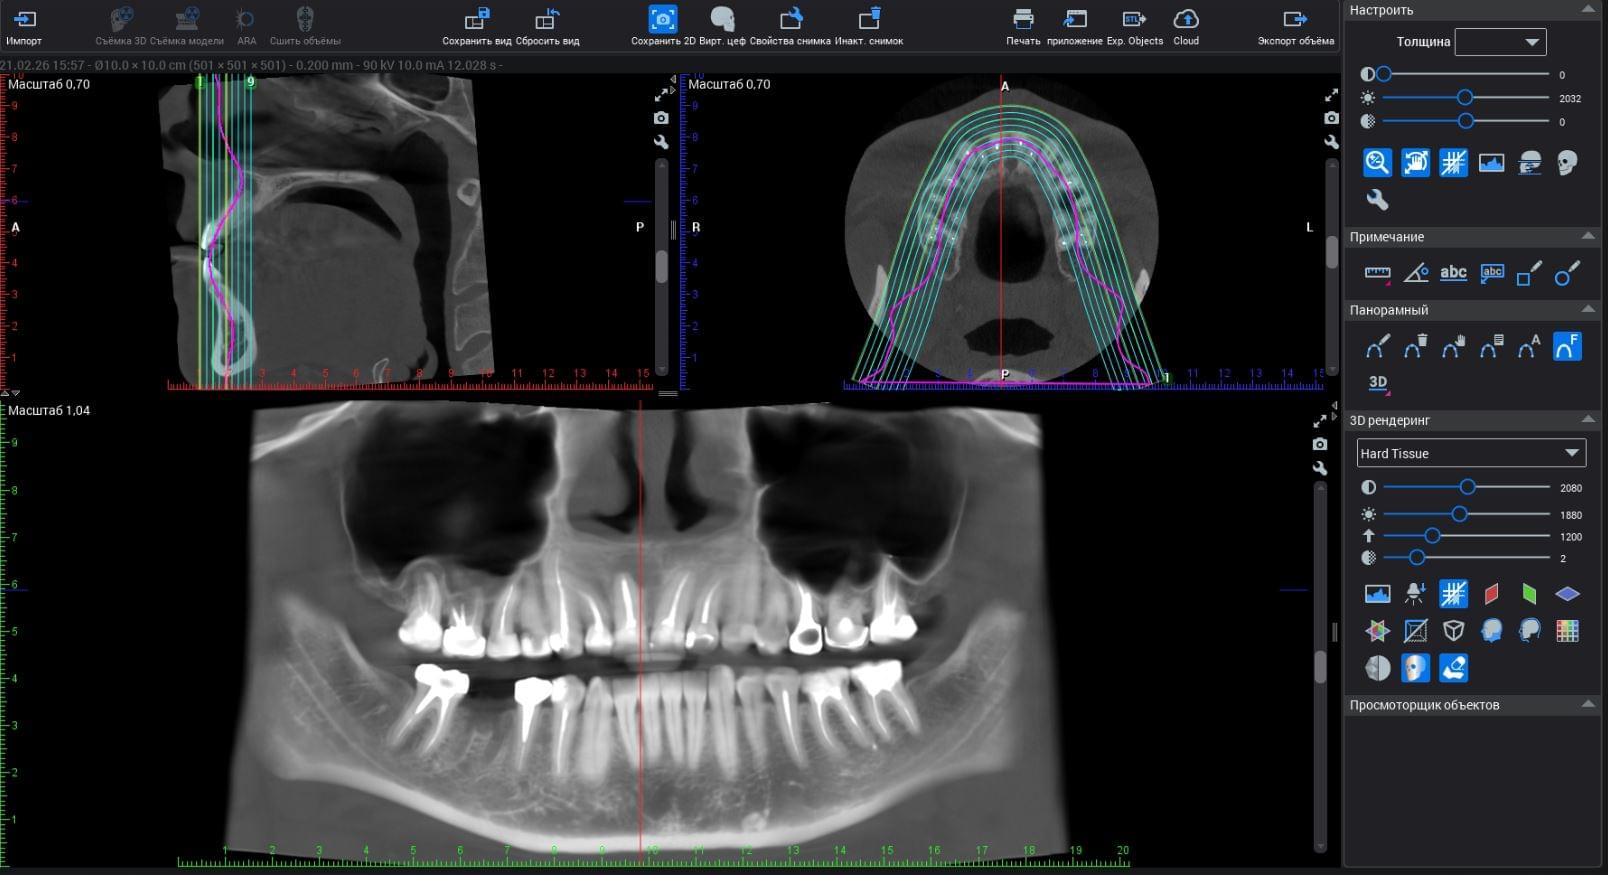

При плануванні імплантації лікарю важливо знати дві речі: об'єм кістки та точне розташування нервів.

КТ дозволяє провести віртуальну операцію: встановити імплант у програмі, виключивши будь-які ризики травмування пацієнта.